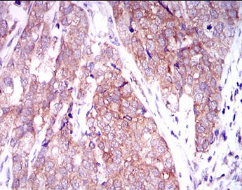

| AC2797 | MARK3 Mouse Monoclonal antibody[2G12] | 100ug | $367 | 10days |

| AC2797 | MARK3 Mouse Monoclonal antibody[2G12] | 200ug | $660.6 | 10days |